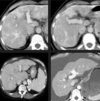

Na TC a avaliação é feita na fase pré-contraste. Avalia-se objetivamente através do valor absoluto e comparativo do ROI (diferença >5 entre fígado e baço) e subjetivamente através da visualização dos vasos.

A

Verdadeiro.